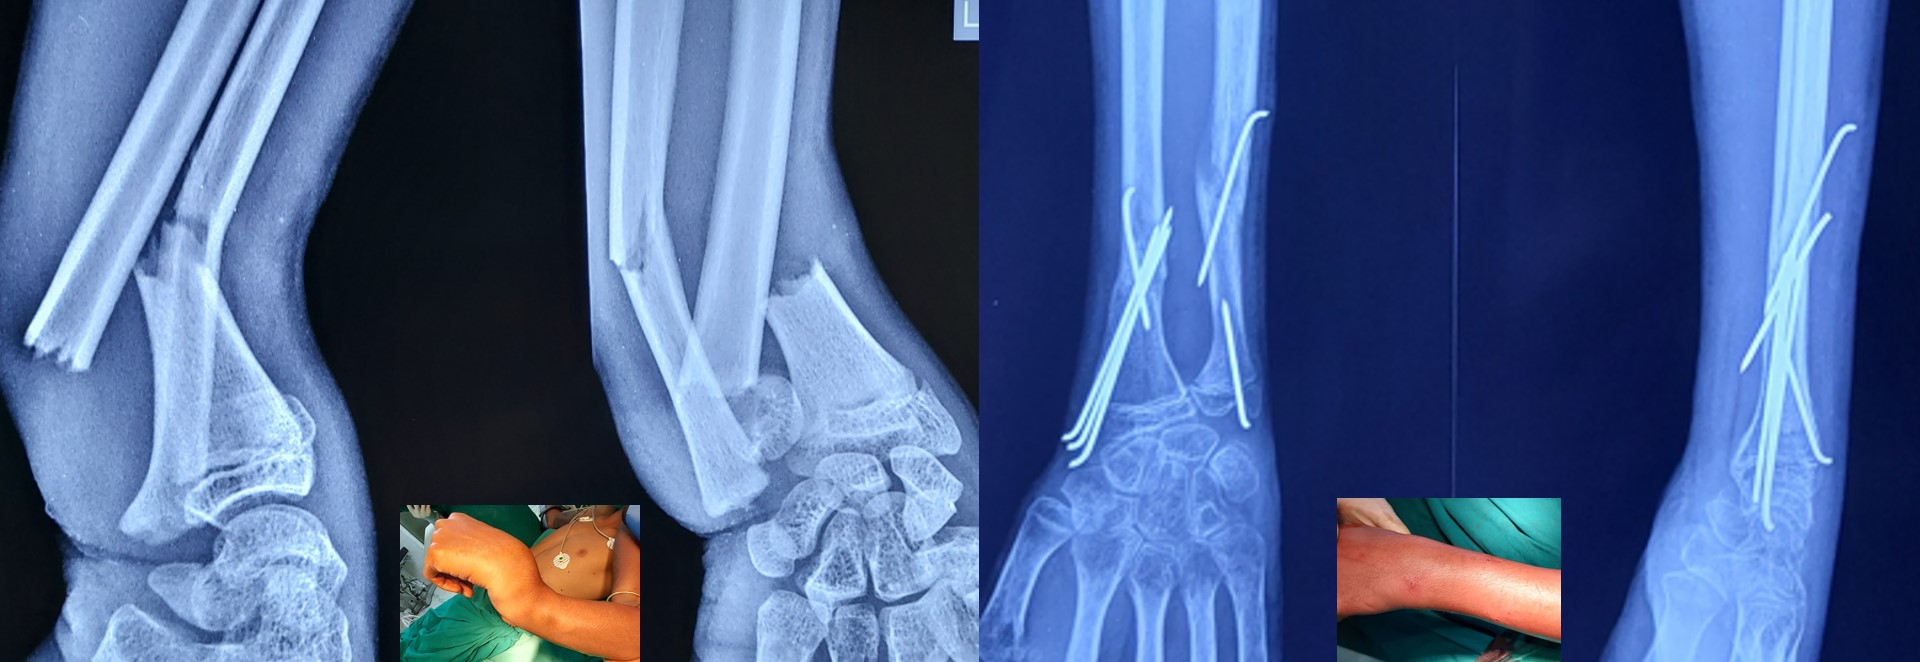

CRPP ( Closed Reduction Percutaneous Pinning )

• No skin incision is required, and fracture heals faster than open surgeries as there is no iatrogenic soft tissue damage or disturbance to the fracture hematoma.

• No implants projecting outside the skin and hence painless adjacent joint movement is possible immediately after CRPP.

• It can be applied to any intraarticular fractures, distal end radius, elbow, ankle and foot.

• Early return to some of the personal works like writing, dressing, washing etc from the 2nd postoperative day onwards after CRPP of the fracture distal radius.